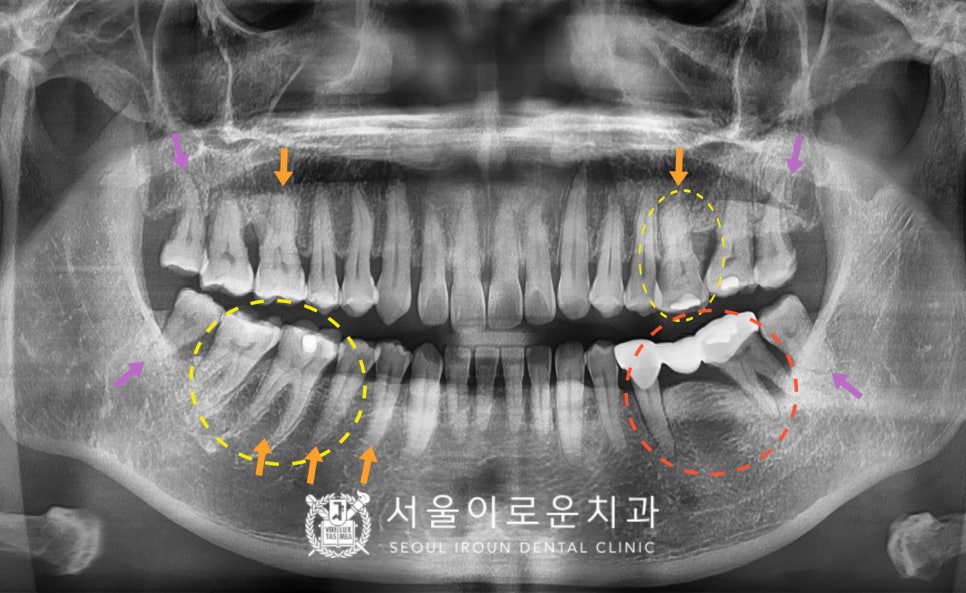

정밀한 검사를 위해

파노라마 사진을 촬영해 보았더니,

제일 불편감을 호소하셨던

빨간 동그라미 표시의

왼쪽 아래 어금니(#35,37) 부위는

기존 브릿지 보철물이

수복 되어 있는 상태였습니다.

보철물 주변 잇몸뼈가

많이 흡수되어 있는 상태로

동요도가 2도 이상으로 많이 흔들려

안타깝게도 살려 쓰기에는 힘든 상황이라

발치 후 임플란트 식립을 계획하였습니다.

또한 보라색 화살표 부위의

사랑니가 4개 모두

맹출이 되어 있었는데요.

사랑니가 맨 안쪽에 위치해 있다 보니

위생관리가 잘되지 않고 있어

추후 다른 치아에까지

영향을 끼칠 것을 고려하여

사랑니 모두 발치를 진행하기로 하였습니다.

확인해 보았더니 주황색 화살표 부위의

치아 허리 부분에 해당하는

치경부가 많이 닳아 있는

치경부마모증이 있었습니다.

노란색 동그라미 표시의 치아들엔

우식이 발견되었는데요.

왼쪽 위 첫 번째 큰 어금니(#26)와

오른쪽 아래 큰 어금니 두 개(#46,47)는

기존 아말감 파절로

기존 충전물이 일부 파절되면서

주변으로 2차 우식이 관찰되었습니다.

또한 오른쪽 아래 두 번째 작은 어금니(#45)는

치.아 원심면에 우식이 보였습니다.